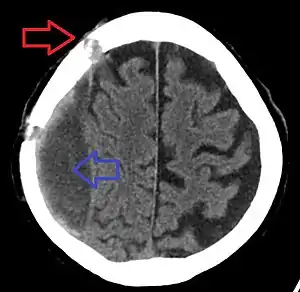

Subdural hematoma as marked by the arrow with significant midline shift

A subdural hematoma (SDH) is when a collection of blood forms between the inner layer of the dura mater and the arachnoid mater of the meninges surrounding the brain.[2] Symptoms may include headache, confusion, personality change, and loss of consciousness.[1] Complications may include brain herniation and seizures.[2]

Subdural hematomas occur most often around the tops and sides of the frontal and parietal lobes.[9][10] They also occur in the posterior cranial fossa, and near the falx cerebri and tentorium cerebelli.[9] Unlike epidural hematomas, which cannot expand past the sutures of the skull, subdural hematomas can expand along the inside of the skull, creating a concave shape that follows the curve of the brain, stopping only at dural reflections like the tentorium cerebelli and falx cerebri.

Chronic subdural after treatment with burr holes

On a CT scan, subdural hematomas are classically crescent-shaped, with a concave surface away from the skull. However, they can have a convex appearance, especially in the early stages of bleeding. This may cause difficulty in distinguishing between subdural and epidural hemorrhages. A more reliable indicator of subdural hemorrhage is its involvement of a larger portion of the cerebral hemisphere. Subdural blood can also be seen as a layering density along the tentorium cerebelli. This can be a chronic, stable process, since the feeding system is low-pressure. In such cases, subtle signs of bleeding—such as effacement of sulci or medial displacement of the junction between gray matter and white matter—may be apparent.